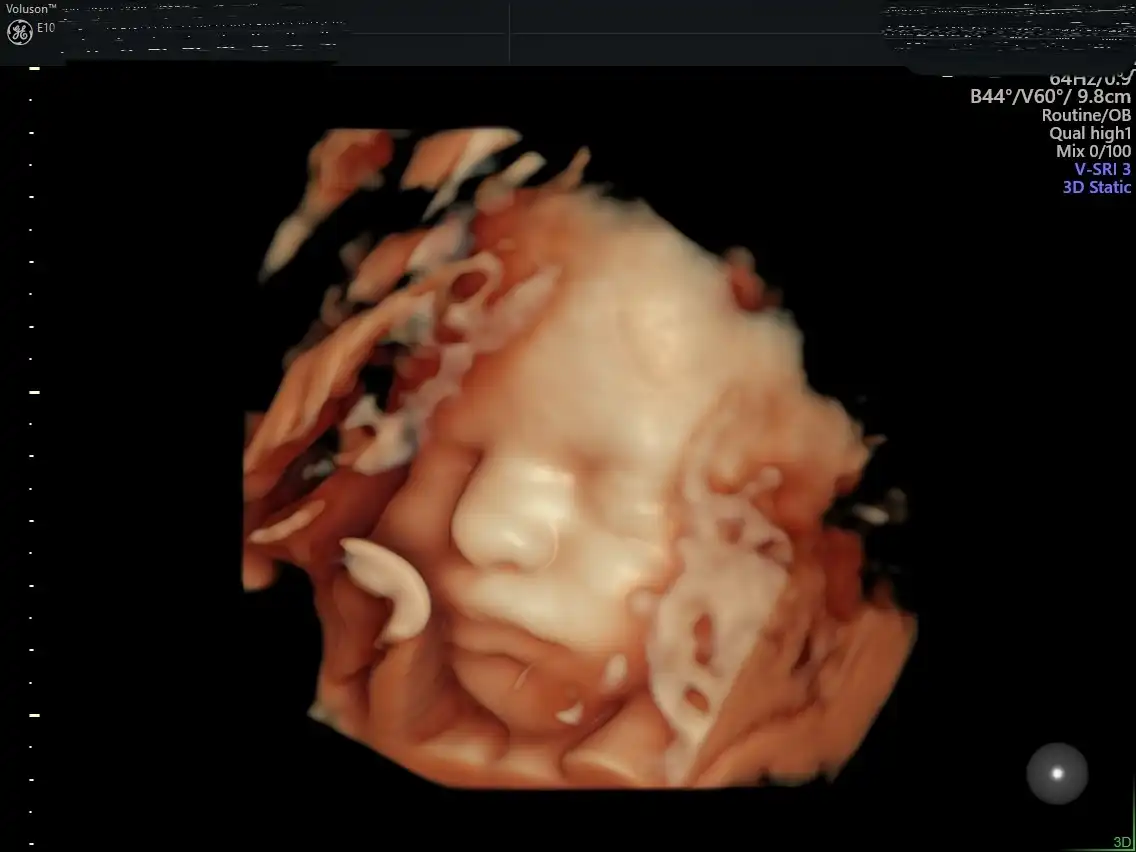

Το Voluson E10 BT19 αποτελεί την αιχμή της τεχνολογίας στην προγεννητική απεικόνιση, προσφέροντας εξαιρετική ευκρίνεια εικόνας, προηγμένη 3D/4D απεικόνιση και υψηλή ταχύτητα επεξεργασίας.

Με εξειδικευμένα εργαλεία για τον προγεννητικό έλεγχο και την καινοτόμο τεχνολογία HDlive™, επιτρέπει λεπτομερή και ρεαλιστική απεικόνιση του εμβρύου, ενισχύοντας τόσο τη διαγνωστική ακρίβεια όσο και την εμπειρία των γονέων.